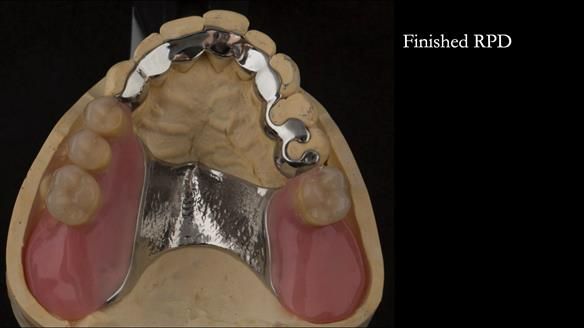

Instead, we made a Scandinavian-style, metal-based lower RPD.

The upper jaw

A metal-based upper RPD was made,

with metal backings incorporated to future-proof the design

should further teeth fail.

The way Rowan lengthened the teeth — particularly in the upper RPD — to match the existing gingival recession on the remaining teeth was superb. The dentures sit naturally within the context of the rest of the mouth.